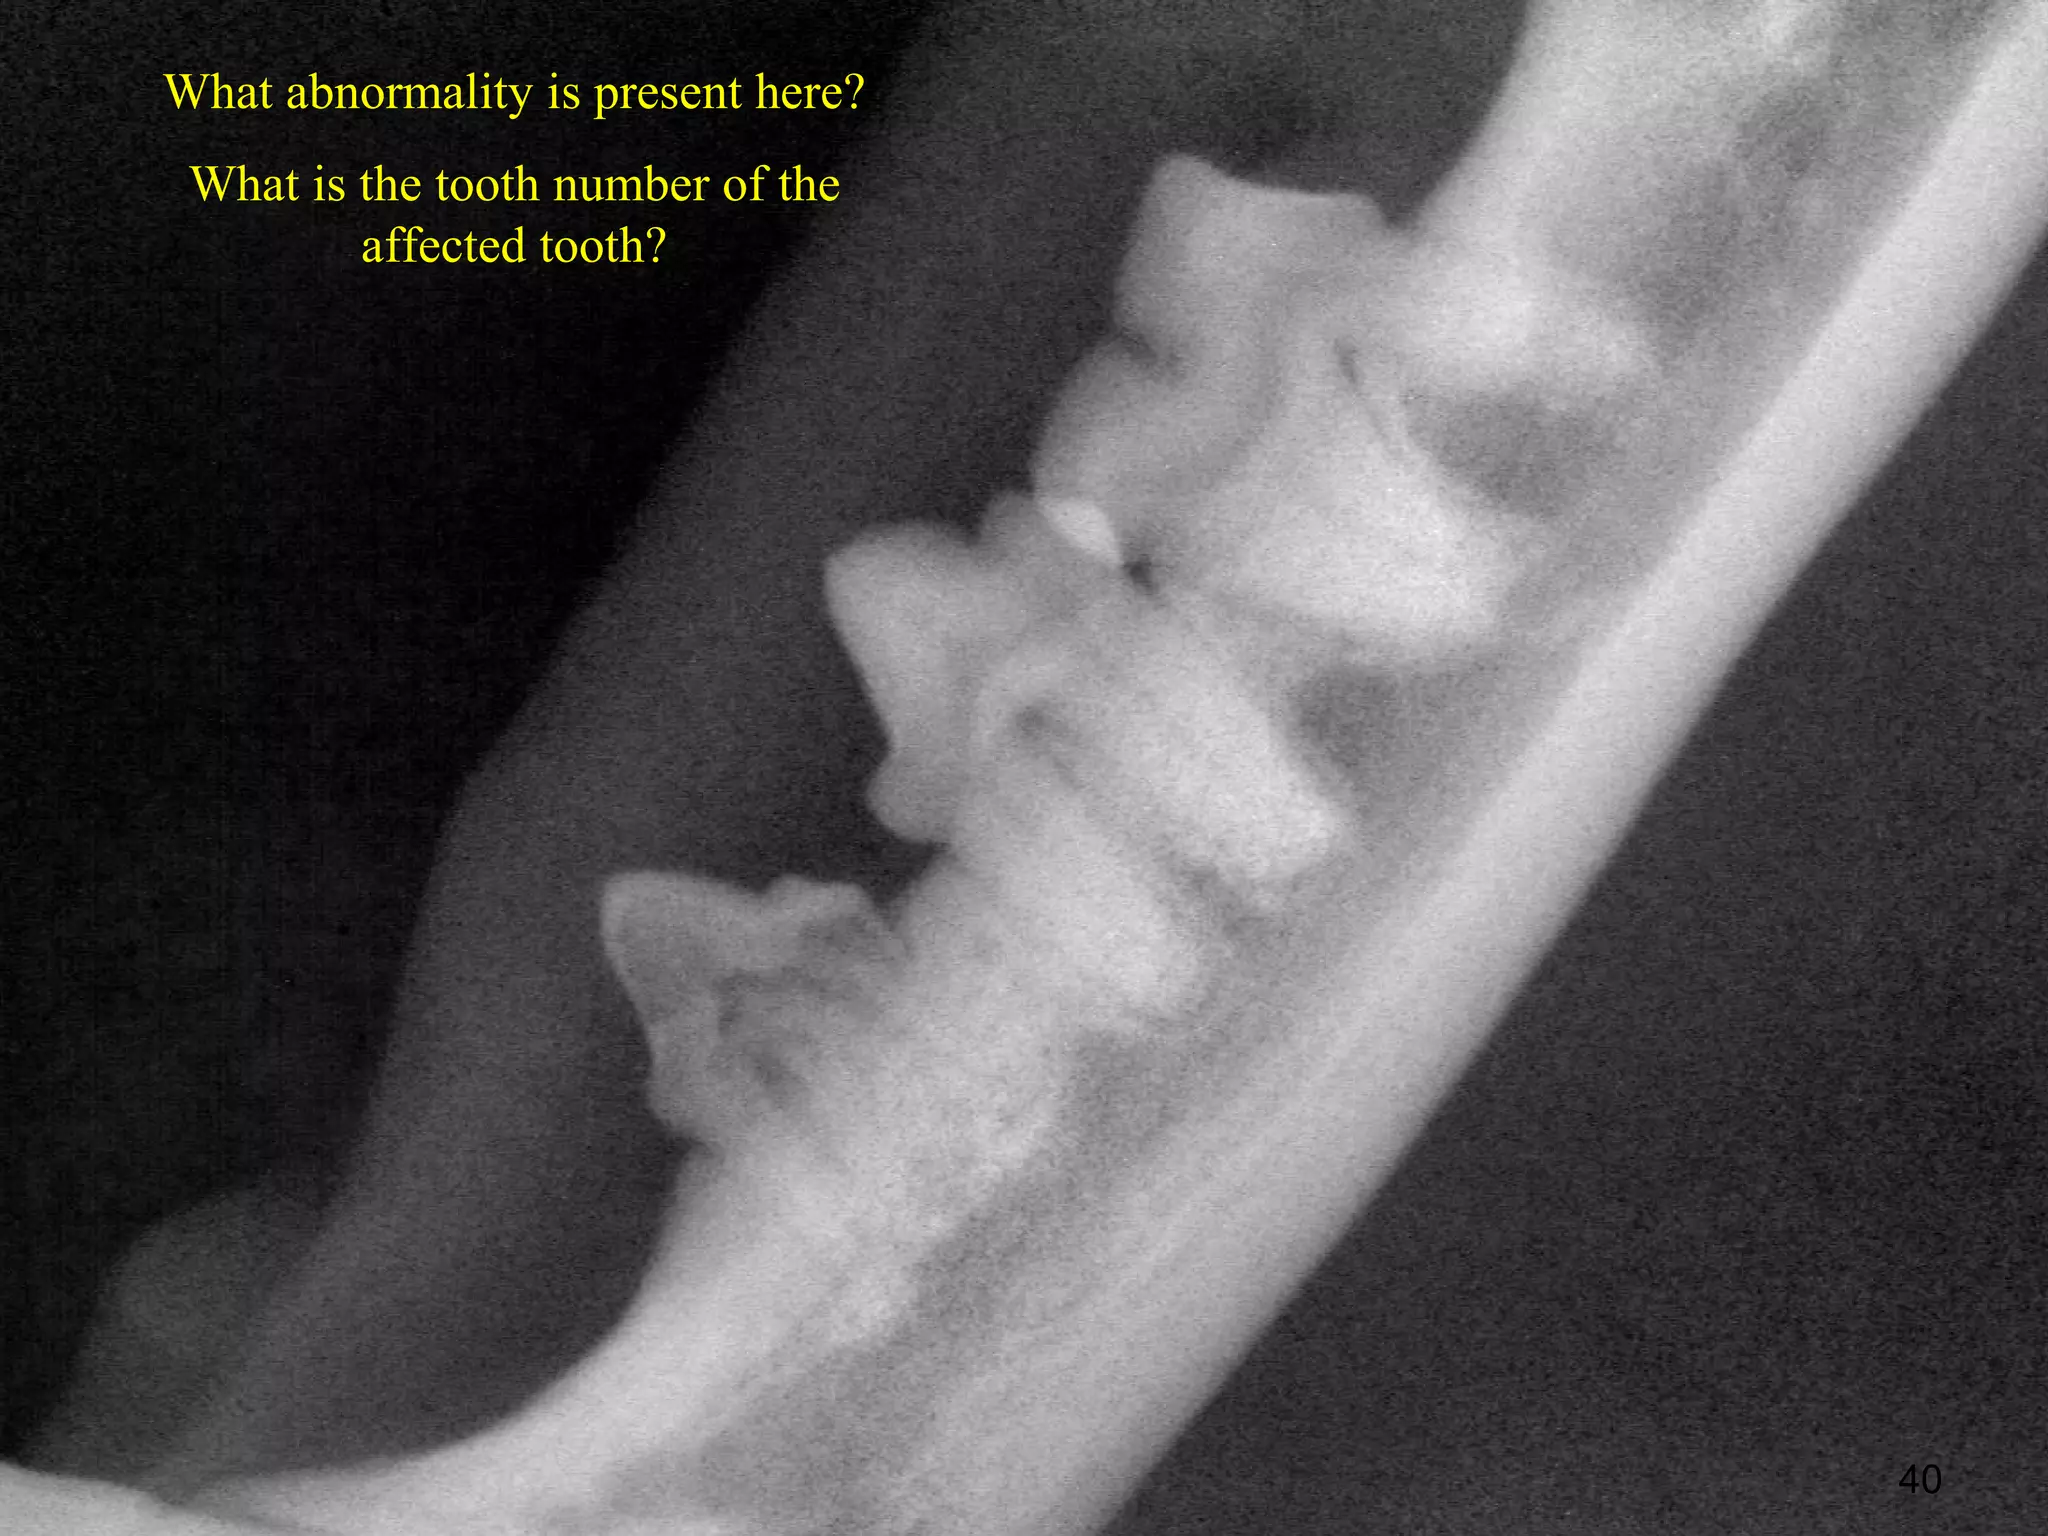

What abnormality is present here?

What is the tooth number of the

affected tooth?

40

What abnormality ispresent here? What is the tooth number of the affected tooth? 40